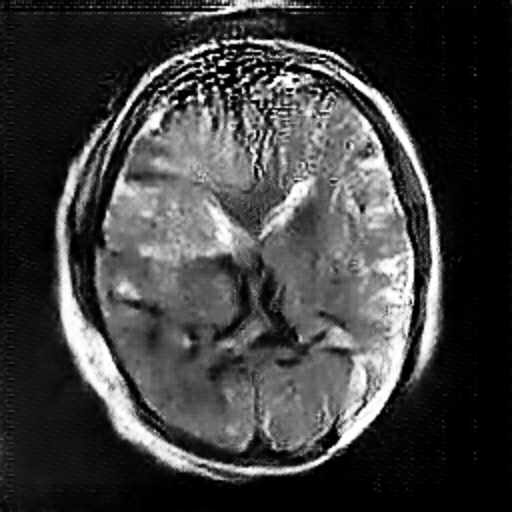

In this study, the data is sourced from Kaggle [7]. In this dataset, there are four subsets for training and testing, which are glioma, meningioma, no tumor, and pituitary. This study will focus on identifying meningioma, so the images in the ‘meningioma’ fold and ‘no tumor’ fold are used. In these two folds, there are a total of 2934 gray-scale images with different sizes. Some sample images can be found in Figure 1.

Figure 1. The sample images of the collected dataset (Left one is no tumor) [7].